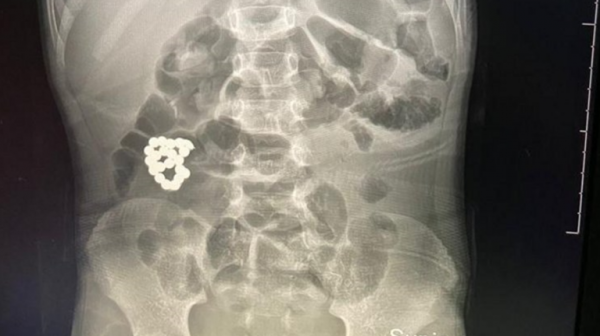

السوسنة -  استطاع فريق طبي بمستشفى الملك عبد العزيز بمدينة جدة السعودية، من إنقاذ حياة طفل، والكشف عن "مفاجأة" كانت في أمعائه.

وفي التفاصيل، تمكن الفريق الطبي بقيادة بروفيسور جراحة الأطفال الدكتور عمر منصور، من إنقاذ حياة طفل في السادسة من عمره، نقل لطوارئ المستشفى يشتكي ألما في البطن يلازمه منذ 4 أيام، وازدادت الآلام مع الوقت، وفق ما أفادت به صحيفة "سبق".

وبعد إجراء الفحوصات اللازمة، أظهرت صور الأشعة وجود جسم غريب في الأمعاء، تبين أنها "إسوارة"، حيث تم إدخال الطفل فورا لغرفة العمليات واستخراج الجسم الغريب، وجرى استئصال الأجزاء المتضررة من الأمعاء في عملية استغرقت ساعتين ونصف الساعة، تكللت بالنجاح.